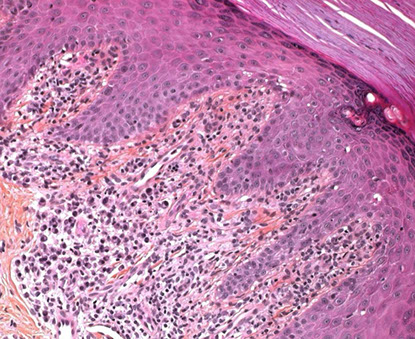

Histo: Epidermal hyperplasia c prominent granular layer (wedge-shaped hypergranulosis) and lichenoid infiltration pattern with irregular epidermal acanthosis causing a sawtooth rete ridges appearance w/o parakeratosis or eos

- Civatte bodies (in epidermis), cytoid bodies, and coloid bodies (Melanoderma???, in papillary dermis) which are apoptotic squames and stain c PAS and Collagen IV

- not likely if parakeratosis is present

- Max- Joseph spaces: subepidermal clefts

Lichen planus

Middle aged pt c lesions on flexor surfaces and in oral mucosal surfaces (in 3 of 4 pts)

- may be assoc c Hep C, but etiology is unknown

- Wickham striae: white lines on surface

- Koebner's phenomenon - scratching spreads the lesion

*** Pruritic Purple Polygonal Papules Planar***